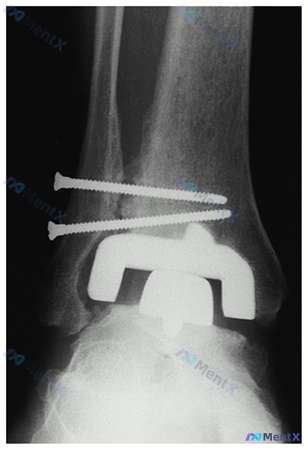

整理到一个有点意思的全踝置换术后病例,容易踩思维陷阱。 > 基本情况: > - 65岁男性,终末期踝关节炎 > - 术前接受过支具、理疗、NSAIDs,效果不佳 > - 行了全踝关节置换术(TAA),术中用了下胫腓联合横向螺钉 > - 术后10个月,仍持续疼痛、行走困难 > 目前检查: > - 手术...